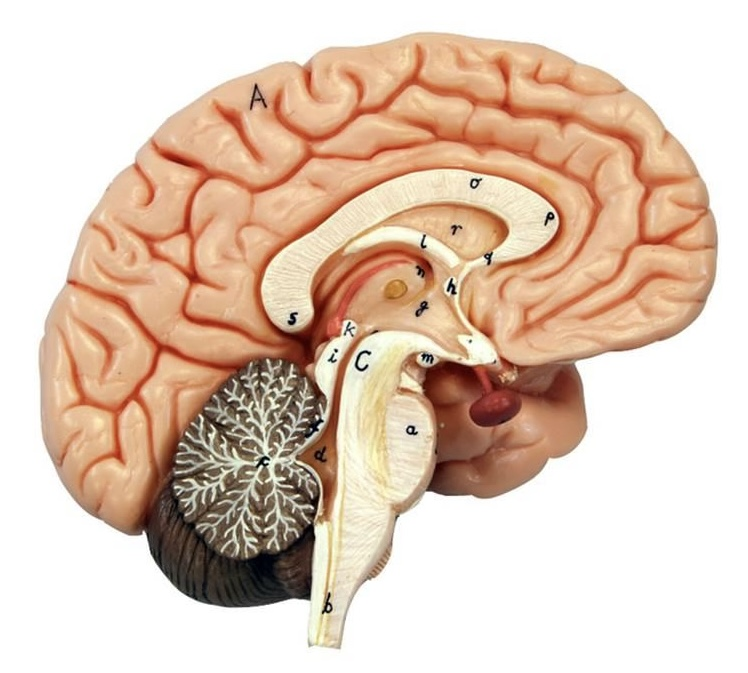

What is D?

lateral ventricle

Imagine thin membrane separating the 2 lateral ventricles

septum pellucidum

What is C?

3rd ventricle

What is B?

cerebral aqueduct

What is A?

4th ventricle

What is below A at the very end?

central canal (spinal cord)

What is C?

midbrain

tectum (corpora quadrigemina): superior colliculus

tectum (corpora quadrigemina): inferior colliculus

What is a?

pons

medulla oblongata

intermediate mass of thalamus

hypothalamus

What is the pink bulb?

pineal gland

corpus callosum

fornix

What is A?

cerebral cortex

cerebral tracts

cerebral hemispheres

longitudinal fissure

What are these ridges?

gyri

What are these shallow grooves?

sulci

Divides parietal from frontal lobe

central sulcus

precentral gyrus

postcentral gyrus